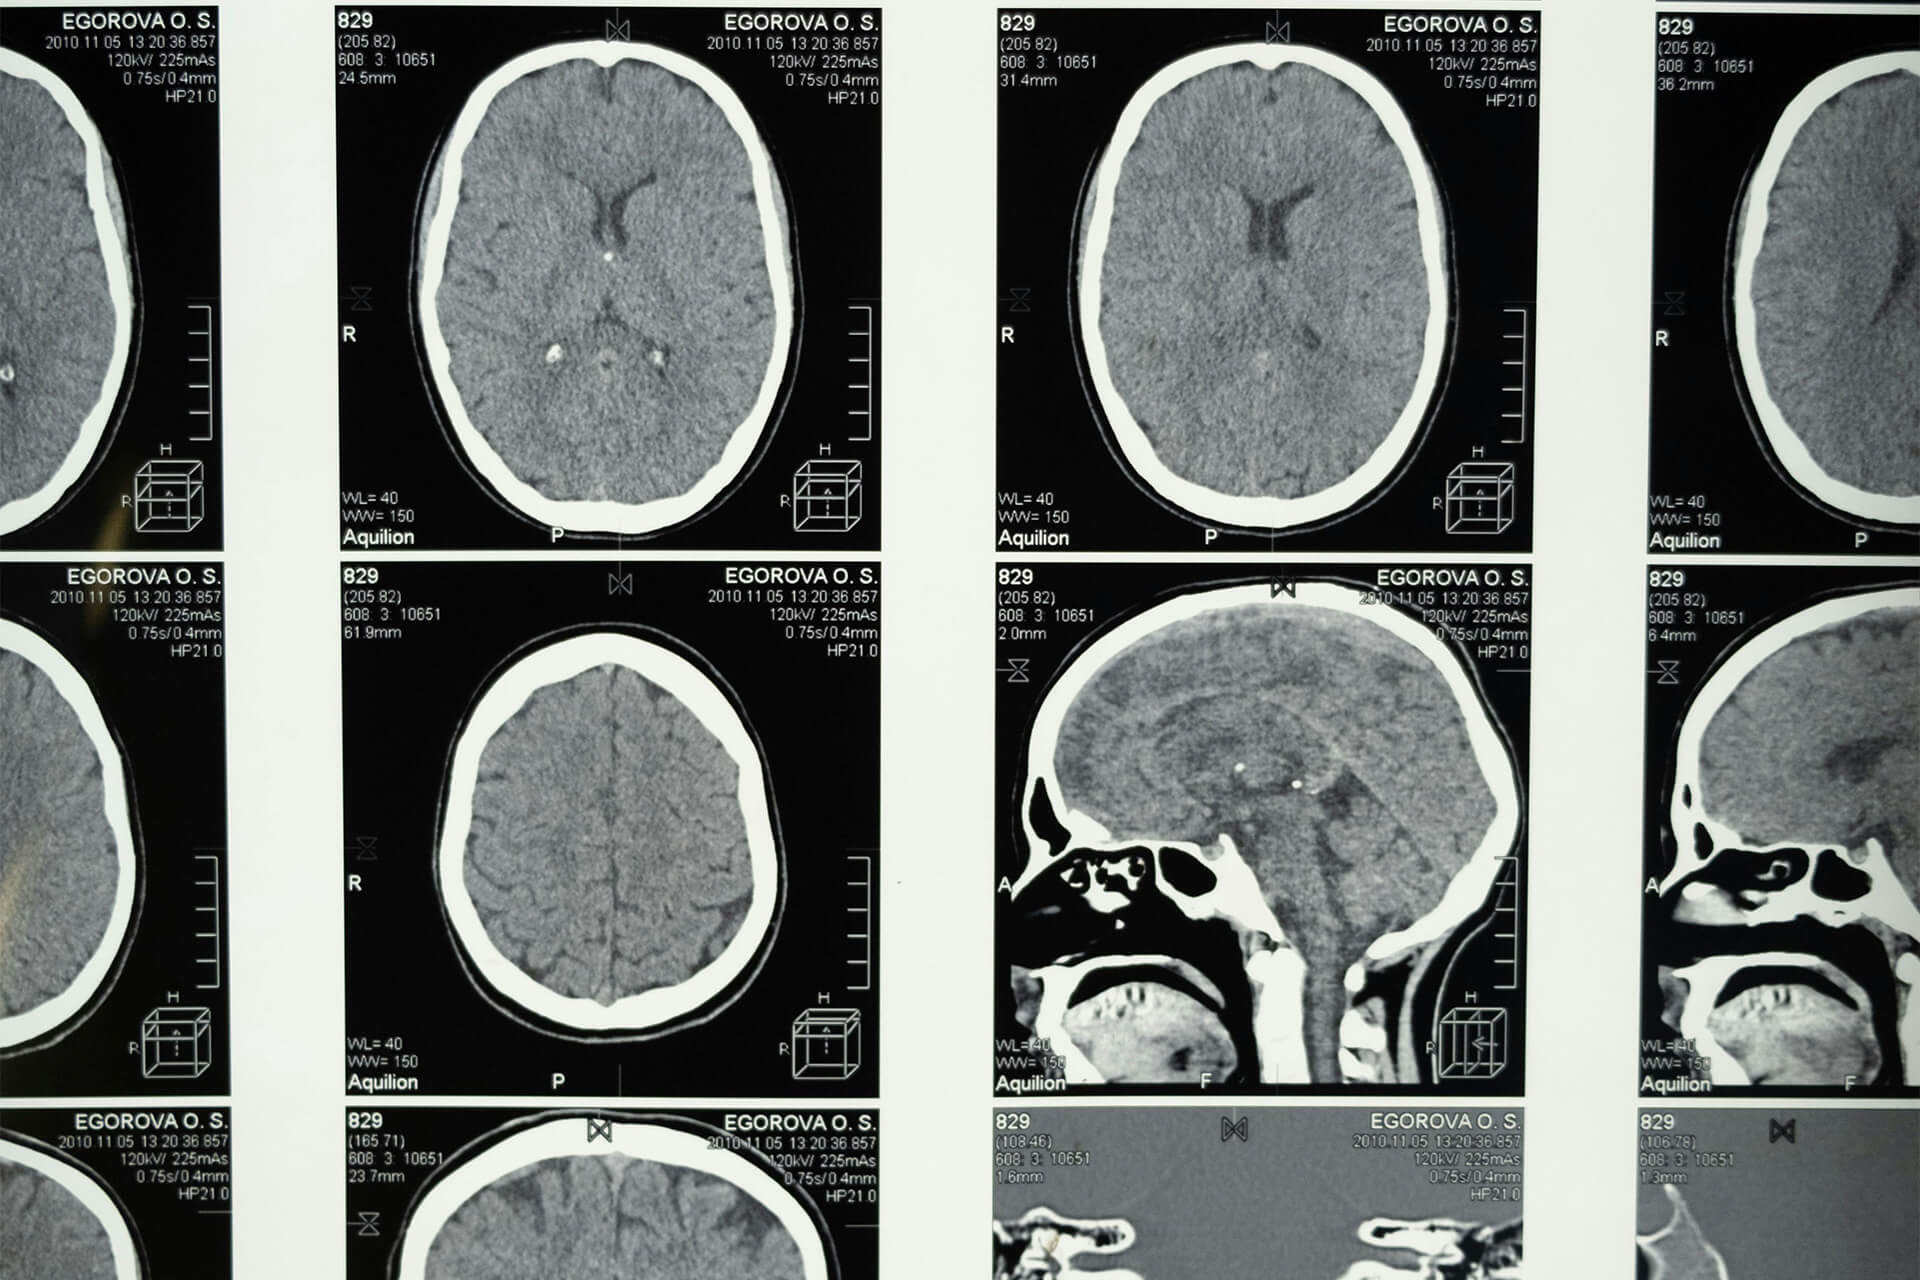

Az MRI vizsgálat, azaz a Mágneses Rezonancia Képalkotás egy kifinomult és forradalmi diagnosztikai eljárás, amely az orvostudomány egyik legfontosabb eszközevé vált. Az MRI vizsgálat során a testbe erős mágneses térrel és rádióhullámokkal keltett rezonanciát használják fel a test belső szöveteinek részletes ábrázolására. Ennek eredményeként lenyűgözően részletgazdag képek készülnek az agyról, a gerincről, az ízületekről, valamint más fontos belső szervekről, amelyek segítenek az orvosoknak pontosabb diagnózist felállítani és hatékony kezelési tervet kidolgozni.

Az MRI vizsgálat széles körben alkalmazható az egészségügyi diagnózisok területén, és olyan betegségek azonosítására is alkalmas, mint agyi daganatok, sclerosis multiplex, gerincproblémák, ízületi elváltozások, szív- és érrendszeri állapotok, valamint különböző daganatos elváltozások. Az orvosok az MRI képeket alapul véve pontosabb és célszerűbb terápiás megoldásokat találhatnak, ami hozzájárulhat a páciensek gyorsabb gyógyulásához és jobb életminőségéhez.

MRI Felvétel

Az MRI felvétel során részletes és háromdimenziós képeket kapunk a vizsgált területről. Ezek a képek segítenek az orvosoknak a pontos diagnózis felállításában és a szükséges kezelés megtervezésében. Az Újbuda Medical Center modern MR készülékei garantálják a kiemelkedő képminőséget minden páciens számára.